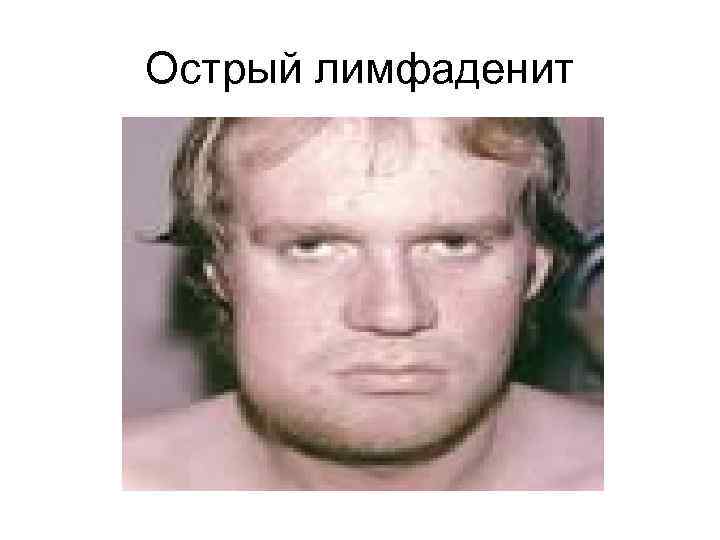

Острый лимфаденит